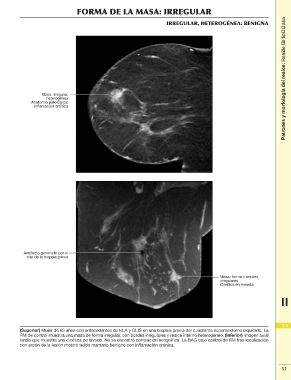

FORMA DE LA MASA: IRREGULAR Patrones y morfología del realce: Realce de tipo masa

IRREGULAR, HETEROGÉNEA: BENIGNA

Masa: irregular,

heterogénea

Anatomía patológica:

inflamación crónica

Artefacto generado por el

clip de la biopsia previa

Masa: forma y bordes

irregulares

Cinética en meseta

(Superior) Mujer de 63 años con antecedentes de HLA y CLIS en una biopsia previa del cuadrante superoexterno izquierdo. La 119

RM de control muestra una masa de forma irregular, con bordes irregulares y realce interno heterogéneo. (Inferior) Imagen axial

tardía que muestra una cinética de lavado. No se encontró correlación ecográfica. La BAG bajo control de RM tras localización 2

con arpón de la lesión mostró tejido mamario benigno con inflamación crónica.